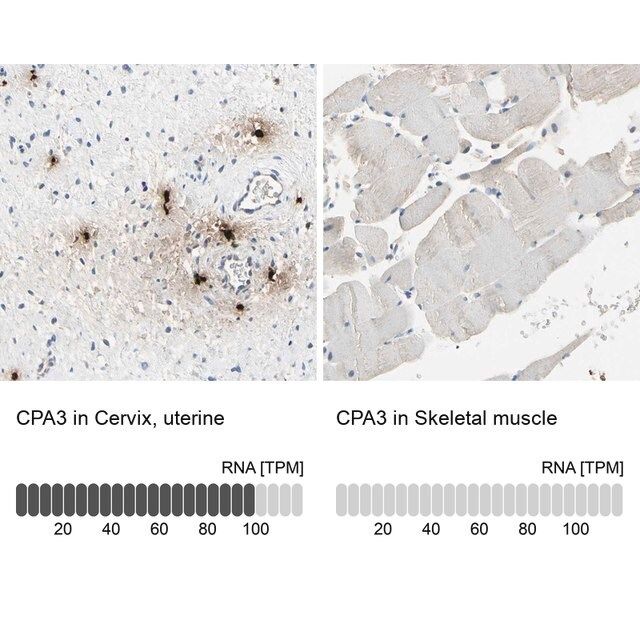

水通道蛋白 4 (aquaporin 4,AQP4) 是一种内源性蛋白,属于水通道蛋白家族,由 13 个成员组成。该基因位于人类 18 号染色体 q11-q12,有 4 个外显子和 3 个内含子。编码的蛋白有 5 个环,由 6 个跨膜结构域干预。环 A、C 和 E 面向浆外区,环 B 和 D 存在于胞浆区。在肺、胃和肾等外周器官中表达。是中枢神经系统表达的主要水通道。它由星形胶质细胞表达,并优先定位于星形胶质细胞的终足突起。它以两种可变剪接形式存在— 长的称为 M1,短的称为 M23。

人类蛋白质图谱项目可细分为三个方面的工作:人类组织图谱、癌症图谱和人类细胞图谱。支持 Tissue and Cancer Atlas 项目而产生的抗体,已经通过免疫组化针对数百个正常和疾病组织进行了测试,通过 Human Cell Atlas 项目最近的努力,很多已经通过免疫荧光法进行了表征,不仅在组织级别,现在也在亚细胞级别绘制了人类蛋白质组图谱。通过点击图像库链接,可以在 Human Protein Atlas (HPA) 位点上查看这些图像和这个庞大数据集的集合。要查看这些协议 和其他有关 Prestige 抗体和 HPA 的有用信息,请访问sigma.com/prestige。

水通道蛋白 4 (aquaporin 4,AQP4) 是脑内主要的水转运体,被认为是维持脑内水分稳态的重要物质。因此,AQP4 可能在脑水肿的发病机制中起重要角色。研究显示,这种转运体在脑缺血中过度表达。因此,它可能有潜力成为缺血性脑水肿的治疗靶点。该基因多态性与脑损伤反应和脑外伤患者的临床预后相关。AQP4 的短亚型 (M23) 有利于颗粒正交排列 (orthogonal array of particles,OAP) 的形成,OAP 的大小由短 (M23):长 (M1) 亚型的比例决定。已知这些 OAP 与视神经脊髓炎 (NMO) 中产生的致病性自身抗体相互作用。因此,对该蛋白的进一步研究可能为 NMO 的发病机制和治疗提供见解。

- 44例正常人类组织以及20例最常见癌症类型组织的IHC组织阵列。